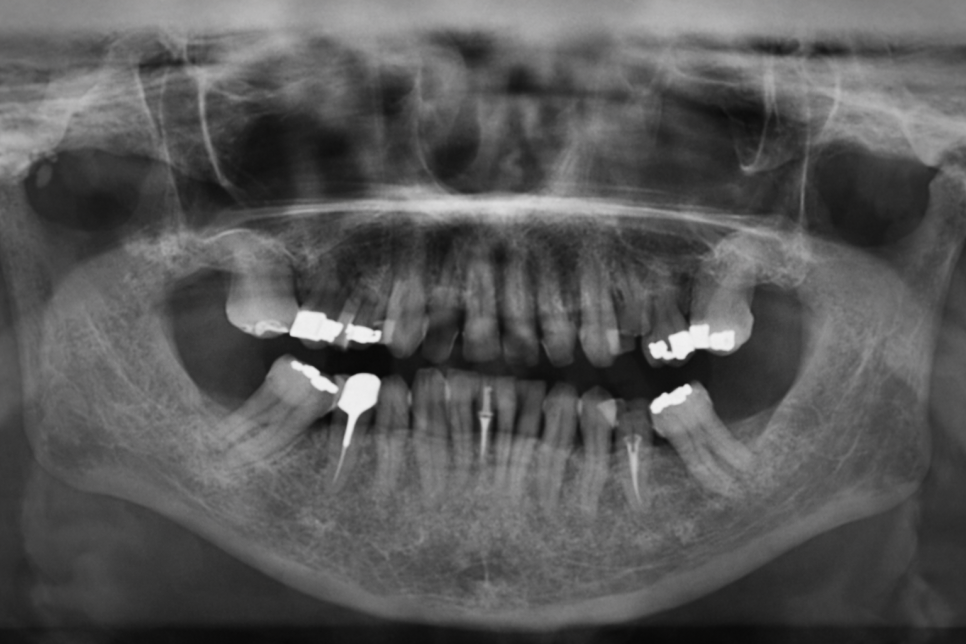

우선 제일 먼저 정밀 검사를 진행합니다.

이를 통해 어떤 문제가 있는지 파악하고

개선하기 위한 적절한 방안을 찾죠.

만약 네이게이션 임플란트가 필요하다 판단되면

추가로 필요한 것들을 체득하게 됩니다.

앞서 촬영한 Panorama와 더불어

CBCT 자료가 필요합니다.

눈으로 봤을 때는 몰랐던

치조골이나 상악동, 하치조 신경관 등

여러 내부 구조를 파악할 수 있는 자료인데,

방사선 사진을 찍어 내부 구조를

체크하는 것뿐만 아니라

수술을 계획하는데 중요한 자료가 됩니다.